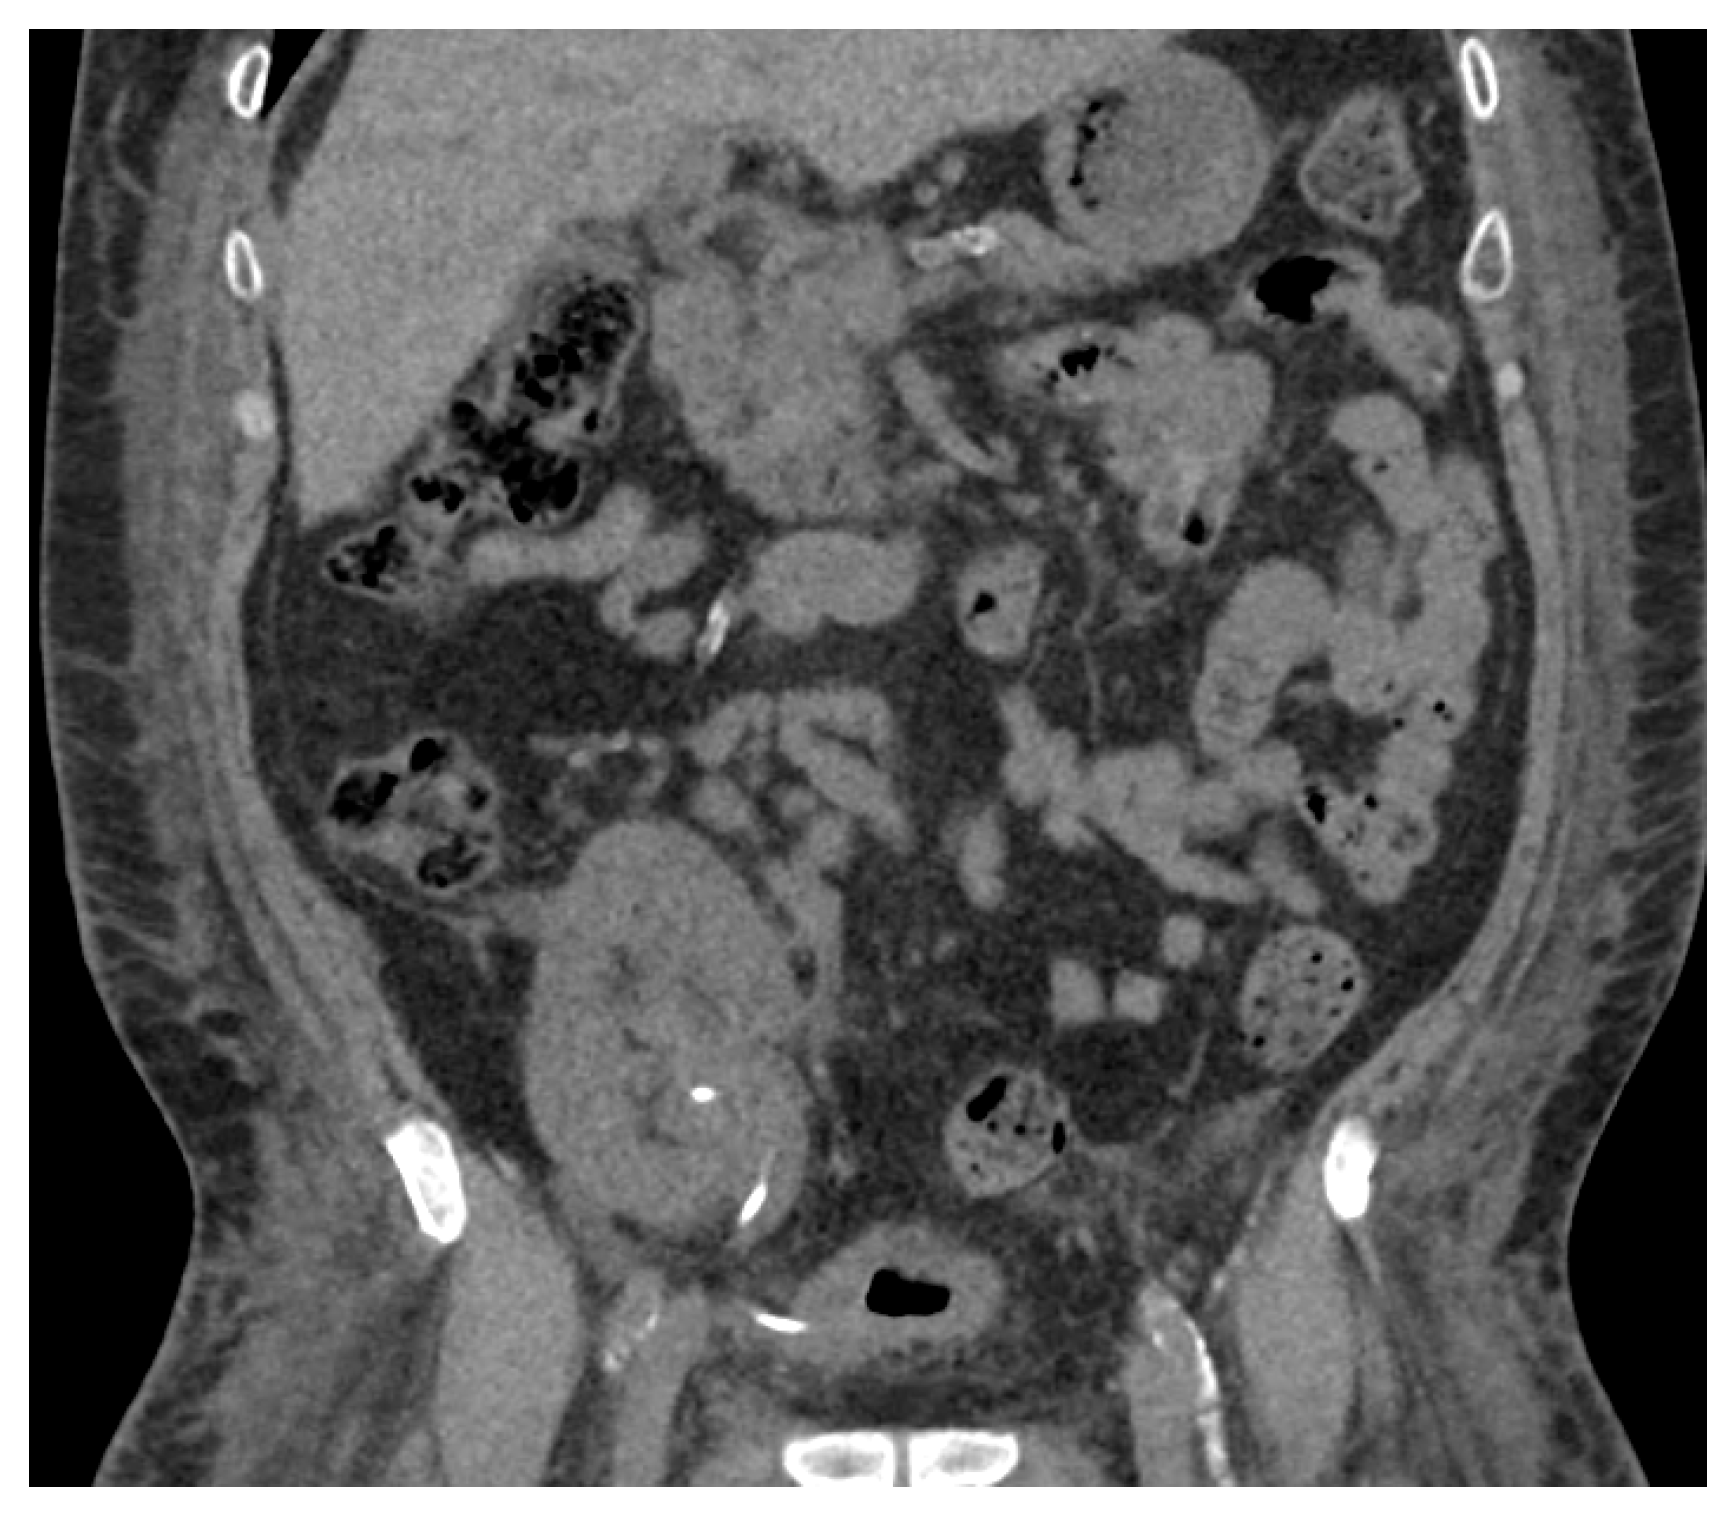

Extensive multidisciplinary discussions led to the decision to perform a percutaneous nephrolithotomy (PCNL). Prior to surgery, the patient developed sepsis with emphysematous pyelitis, interval worsening of hydroureteronephrosis, and acute kidney injury (AKI) (Figure 6). A transplant nephrostomy tube was placed for urgent renal decompression and the patient was discharged after the resolution of sepsis and AKI.

Figure 6. Non-contrast CT during episode of sepsis. (A) Coronal image demonstrated interval worsening of hydroureteronephrosis with gas within the renal collecting system and bladder consistent with emphysematous pyelitis. (B) Axial image demonstrated splitting of the large, calcified material into two separate soft tissue densities with rim calcification, each measuring between 2.5 and 2.8 centimeters at the ureteropelvic junction.